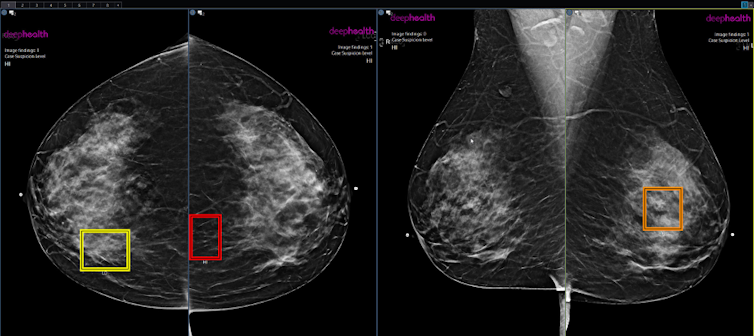

The AI products I looked at are designed to detect abnormalities such as tumours or vessel blockages on breast X-rays and brain CT scans, which are crucial indications for breast cancer and stroke.

Demonstration of AI models detecting tumours on breast X-rays.

Radiological Society of North America